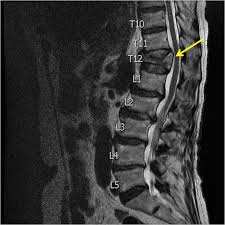

Over the weekend i have been experiencing pins and needles in my right hand and arm, a sensation of someone pouring cold water on my left thigh and. The fracture line breaches both the anterior and posterior vertebral body cortex and the anterior superior endplate. A compression fracture is a type of fracture or break in your vertebrae. They often occur in the upper lumbar segments as well, such as l1. In the lumbar region, where the most axial load is, the vertebrae of level l (1 and 2) are injured. Compression fractures are the most common type of fracture affecting the spine. Compression fractures of the spine generally occur from too much pressure on the vertebral body. A compression fracture of a spine bone (vertebra) causes the bone to collapse in height. The doctor suggested bracing for three. Individuals that have been diagnosed with osteoporosis are very prone to developing small fractures in the spine, eventually leading to a compression fracture. The vertebrae are the bones in your back that are stacked on top of each other compression fractures can cause the vertebrae to collapse, making them shorter in height. Apply the one that makes the injury feel better. One and a half years back i got a compressed l1 fracture as a result of a car accident.

A t12 or l1 compression fracture most commonly happens as a wedge fracture, which occurs when the front part of the vertebra collapses compression fracture treatment options vary depending on the cause.

They often occur in the upper lumbar segments as well, such as l1. Nonsurgical options include activity restrictions, physical therapy, and treating osteoporosis. Related online courses on physioplus. Over the weekend i have been experiencing pins and needles in my right hand and arm, a sensation of someone pouring cold water on my left thigh and. Vertebral compression fractures | american association of neurological surgeons. Burst compression fracture of the l1 vertebral body is associated with a 35% loss of vertebral body height. Rarely, compression fractures occur in healthy vertebrae as a result of trauma. Lumbar compression fractures can be a devastating injury, therefore, for 2 reasons.

First, the fracture itself can cause significant pain, and media gallery. Applying heat in the first few days after an injury draws more blood to the injury site, thus. There is a 3 mm retropulsion into the spinal canal, resulting in only mild canal. Lumbar compression fractures can be a devastating injury, therefore, for 2 reasons. Compression fractures tend to heal completely in about 8 to 12 weeks. More often, the vertebra with a. Vertebral compression fractures | american association of neurological surgeons. Rarely, compression fractures occur in healthy vertebrae as a result of trauma. Anteroposterior and lateral radiographs of an l1 osteoporotic wedge compression fracture. Compression fractures of the spine usually occur at the bottom part of the thoracic spine (t11 and t12) and the first vertebra of the lumbar spine (l1). The fracture line breaches both the anterior and posterior vertebral body cortex and the anterior superior endplate. Apply the one that makes the injury feel better. A compression fracture is a type of fracture or break in your vertebrae.